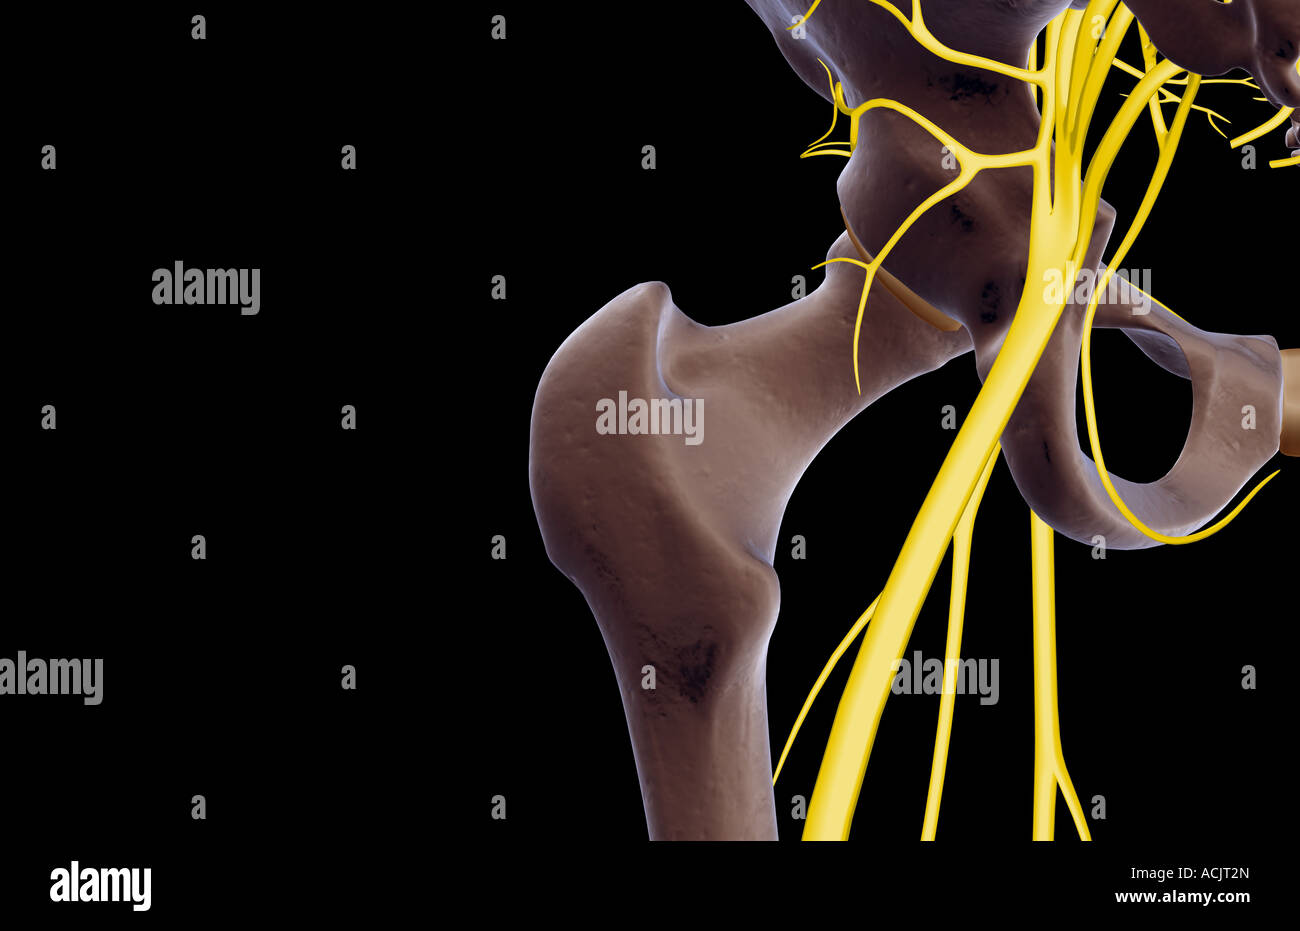

Les nerfs de la hanche Banque D'Imageshttps://www.alamyimages.fr/image-license-details/?v=1https://www.alamyimages.fr/photo-image-les-nerfs-de-la-hanche-13173020.html

Les nerfs de la hanche Banque D'Imageshttps://www.alamyimages.fr/image-license-details/?v=1https://www.alamyimages.fr/photo-image-les-nerfs-de-la-hanche-13173020.htmlRFACJT2N–Les nerfs de la hanche